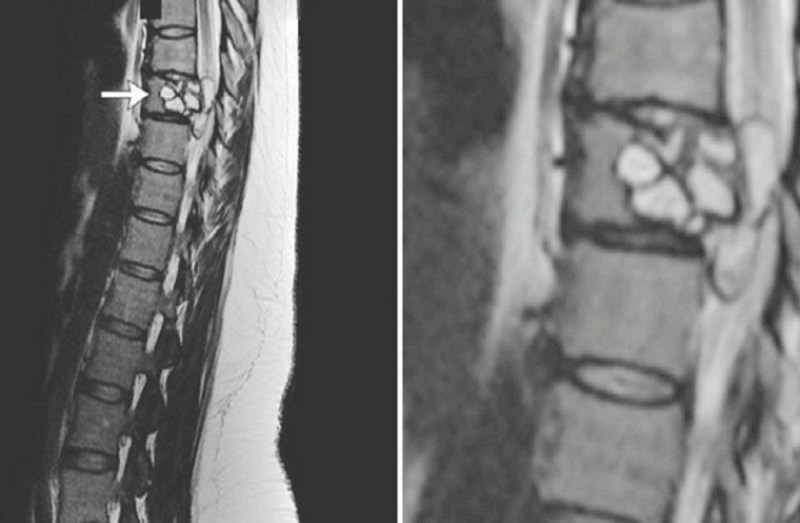

नई दिल्ली। जब एक महिला को डॉक्टरों ने बताया कि उसकी रीढ़ की हड्डी में एक कीड़े ने घर बना लिया है तो उसके पैर कांपने लगे। यूं तो कभी-कभी शरीर में ऐसे कुछ परजीवी हमारे शरीर में जाने-अनजाने दाखिल हो जाते हैं और हमें पता भी नहीं चलता। ऐसे कई केस हमें आए दिन देखने सुनने को मिलता है।आज एक और ऐसा ही केस आपको बताने जा रहे हैं जो आपको भी बहुत हैरान कर देगा। 35 वर्षीय इस फ्रांसीसी महिला का कहना है कि, उसे पिछले तीन महीनों से चलने में मुश्किल हो रही थी और वो बार-बार गिर जाती थी। जब उसकी रीढ़ का एमआरआई किया गया तो पता चला कि एक खरतनाक जीव उसकी रीढ़ की हड्डी में छिपकर बैठा है ये परजीवी आमतौर पर कुत्तों में पाया जाने वाला एक टेपवॉर्म होता है।

एक मीडिया रिपोर्ट के अनुसार, फ्रांस से आए मामले में सामने आया है पिछले तीन महीनों से उसकी रीढ़ की हड्डी में टैपवार्म है। इसी के कारण उसे चलने में काफी दिक्कत हो रही थी। महिला ने बताया कि वह केवल अपने पालतू बिल्ली, घोड़ों और मवेशियों के संपर्क में आई थी, इसलिए वैज्ञानिकों को भी हैरानी थी कि ये परजीवी उसके शरीर में दाखिल कैसे हुआ जो सिर्फ कुत्तों में ही पाया जाता है। महिला का इलाज हुआ और उसकी सर्जरी में जीव को डॉक्टर सफलतापूर्वक हटाने में कामयाब भी रहे, अध्ययन करते समय echinococcus granulosus नाम का जीव पाया गया, जो आमतौर पर मनुष्यों में नहीं मिलता है। इस तरह के टेपवॉर्म संक्रमण का कारण बन सकता है जो यकृत और फेफड़ों में सिस्टिक घावों का कारण बन सकता है, और केंद्रीय तंत्रिका तंत्र और हड्डियों को भी नुक्सान पहुंचा सकता है। दुर्भाग्यपूर्ण महिला का एंटीपारासिटिक दवा के साथ इलाज किया गया और उसे पूरी तरह से ठीक किया गया आज वो खुद के पैरों पर खड़ी है।